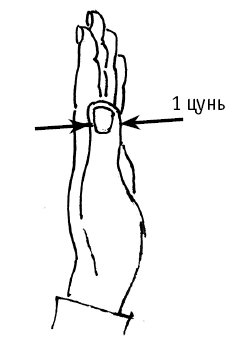

Чтобы отмерить 1 цунь от сгиба запястья, надо приложить большой палец (см. рис. 1). Причем мужчина должен приложить левый палец, а женщина – любой (если, конечно, ее ремесло не предполагает уплощение пальца, как у пряхи, например).

1 цунь – это ширина большого пальца левой руки (у мужчин) по линии, проходящей через угол ногтевого ложа (рис. 1). У женщин можно использовать для измерения обе руки.

Чтобы отмерить 1 цунь от сгиба запястья, надо приложить большой палец (см. рис. 1). Причем мужчина должен приложить левый палец, а женщина – любой (если, конечно, ее ремесло не предполагает уплощение пальца, как у пряхи, например).

1 цунь – это ширина большого пальца левой руки (у мужчин) по линии, проходящей через угол ногтевого ложа (рис. 1). У женщин можно использовать для измерения обе руки.